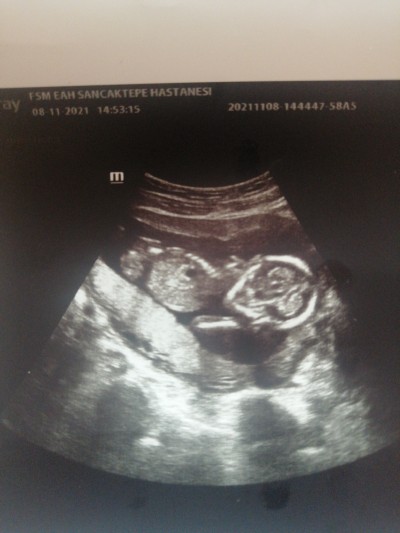

Bugün muayene günümdü 16 haftalık olmama rağmen doktor göremedi görebilen varsa yardımcı olabilir mi

Gebelik haftası 16+0